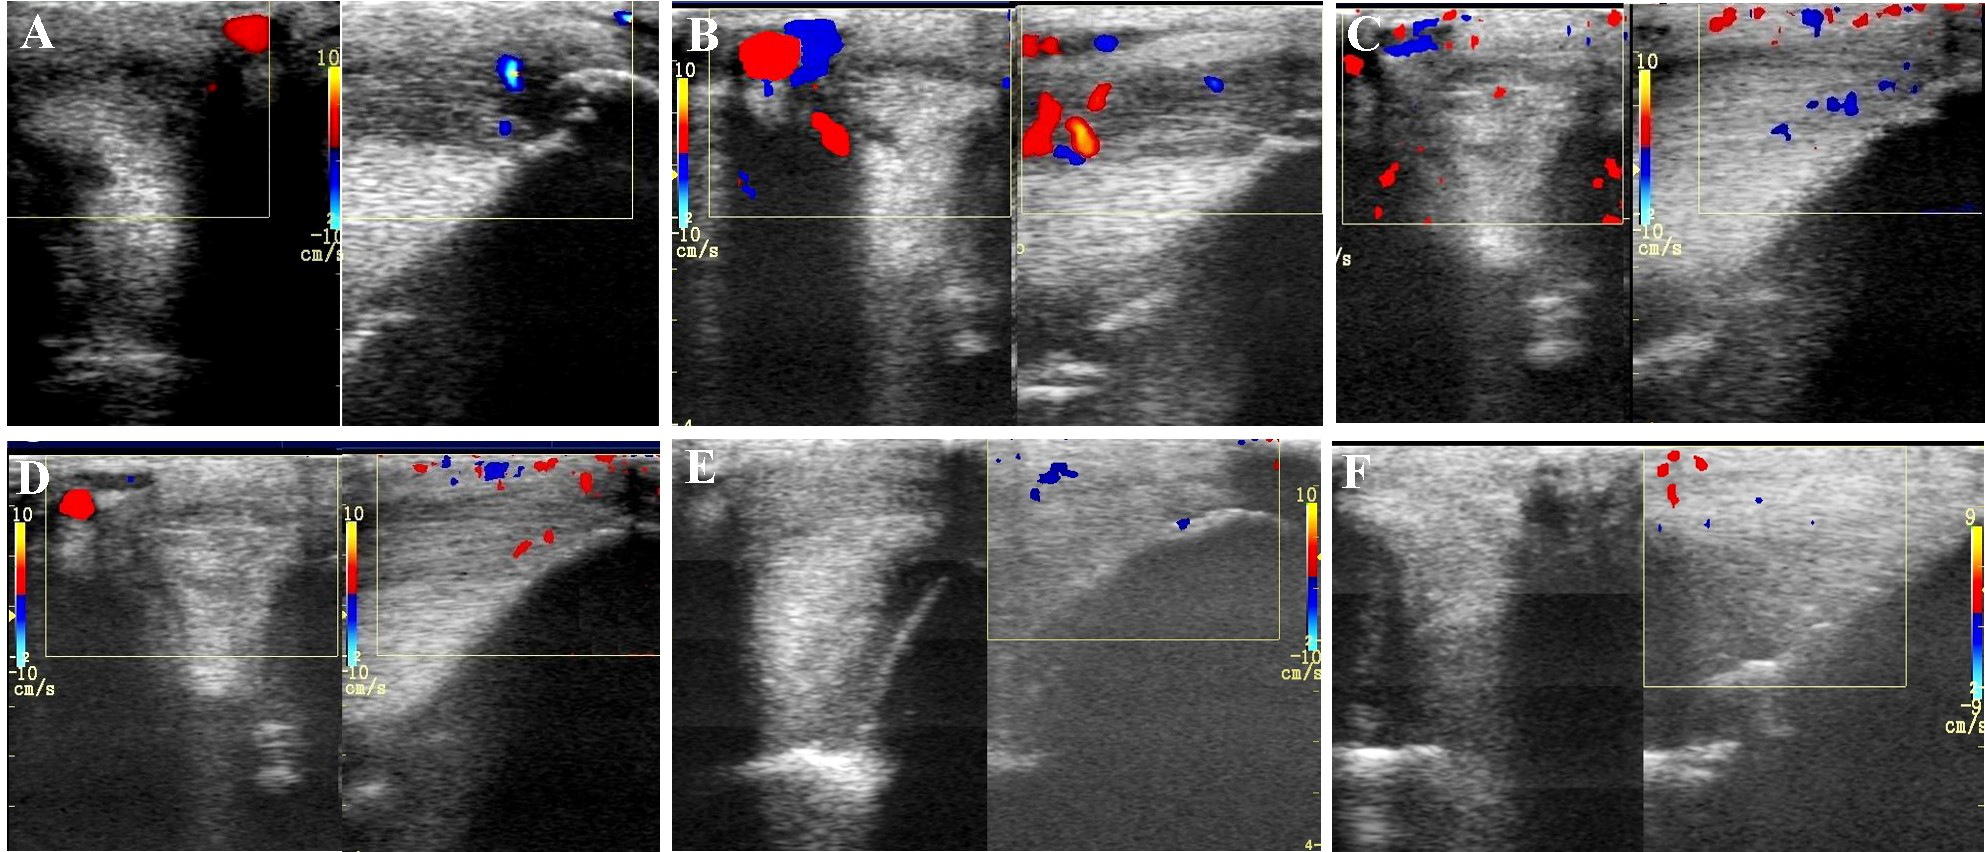

FIGURE 3

Ultrasound images prior to plasmid DNA encoding VEGF164 and FGF2 genes on day 0 (A), 20 (B), 40 (C), 90 (D), 180 (E), and 300 (F) after administration in horse #2 – SLB desmopathy. Arrows indicate lesion.

The evaluated T/L lesions using CDU showed that in most horses with SLB-desmopathy before treatment, only small color foci that were rhythmically blinking at the lesion area were present. The average color Doppler scores for vascularization of maximal inquires zone for SLB before treatment was 1.27 (±0.21), this was slightly elevated in comparison to healthy contralateral limbs (0.8 ± 0.52). Color Doppler scores for vascularization of maximal inquires zone for SLB limbs after treatment with the plasmid DNA encoding VEGF164 and FGF2 genes, revealed a notable increase in scores by just day 20 (2.97 ± 0.93; Table 4 and Figures 4, 5). The increase continued at day 40 (0.03 ± 0.68), with elevated levels continuing until day 90. The CDU scores in most animals then gradually decreased to basal indices (as in healthy limbs) after 180 days of treatment, indicating blood flow patterns similar to day 0 (Figure 4). No significant correlation was observed between the severity of T/L lesions prior treatment and CDU scores after treatment. Horse #2 after 20 days of treatment showed a very high CDU score of 4. This horse, as previously mentioned, had a slight local reaction on days 5–10 at the site of plasmid DNA injection.